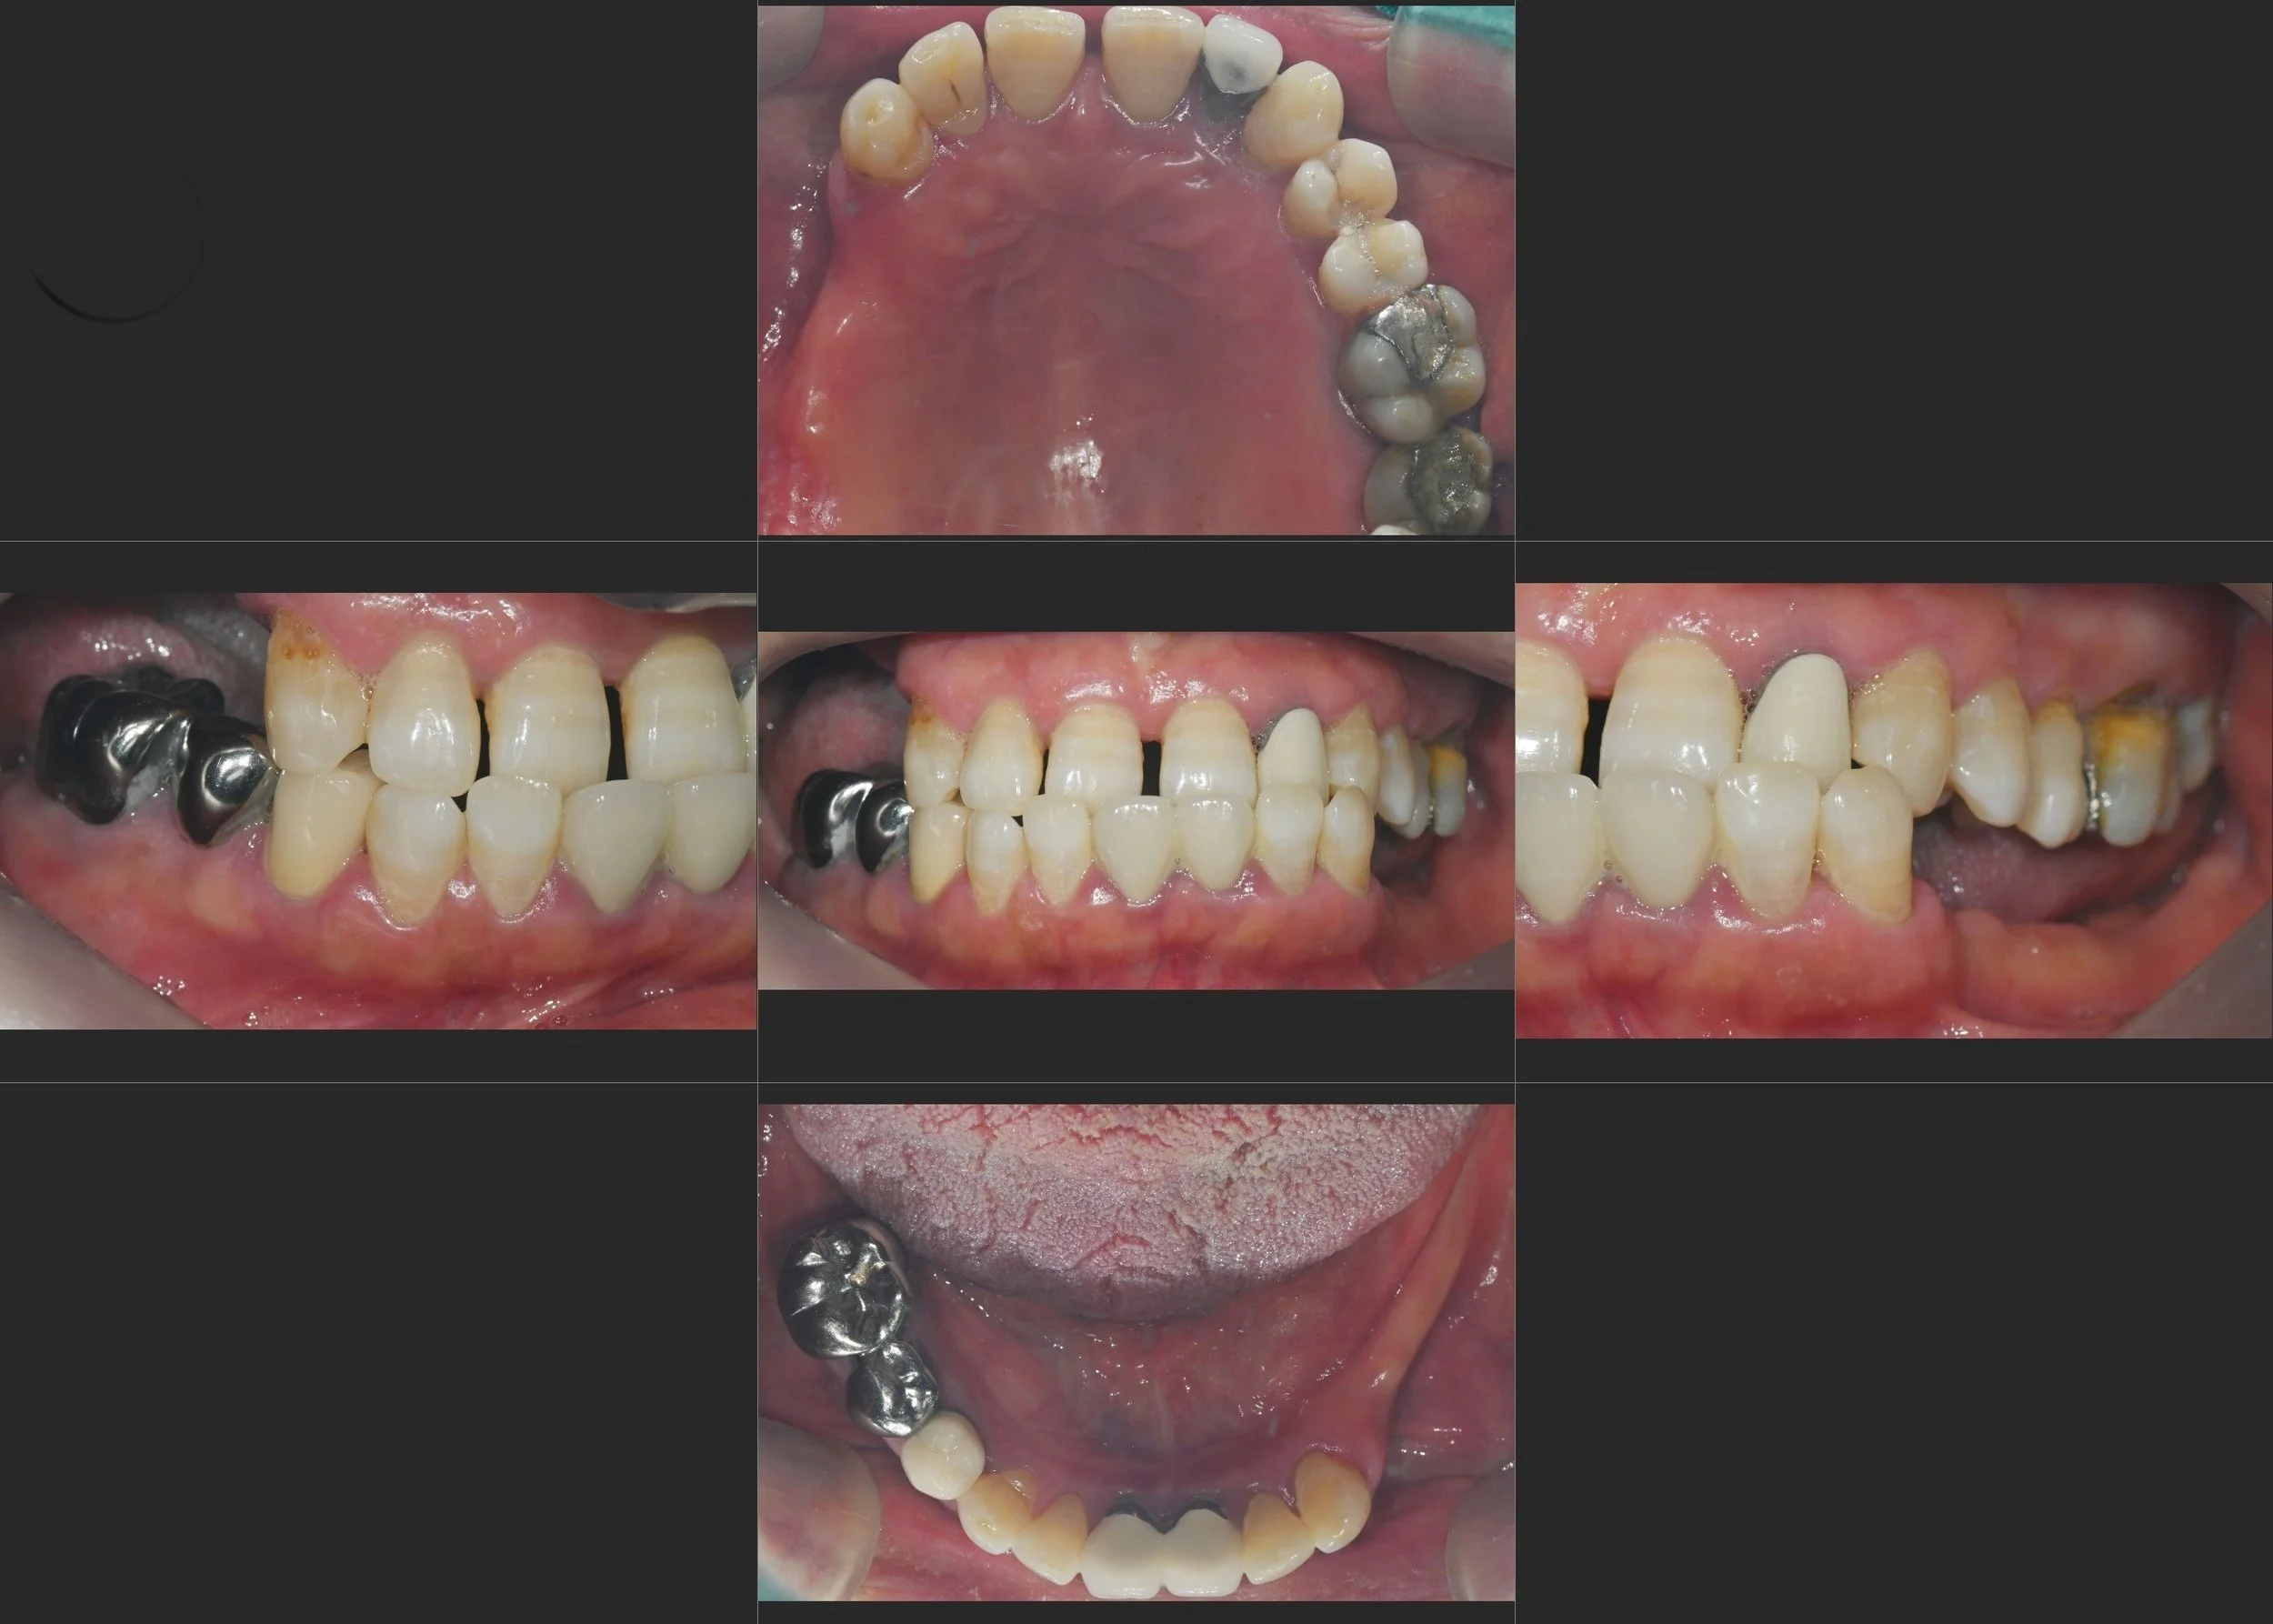

INTRA ORAL - AFTER